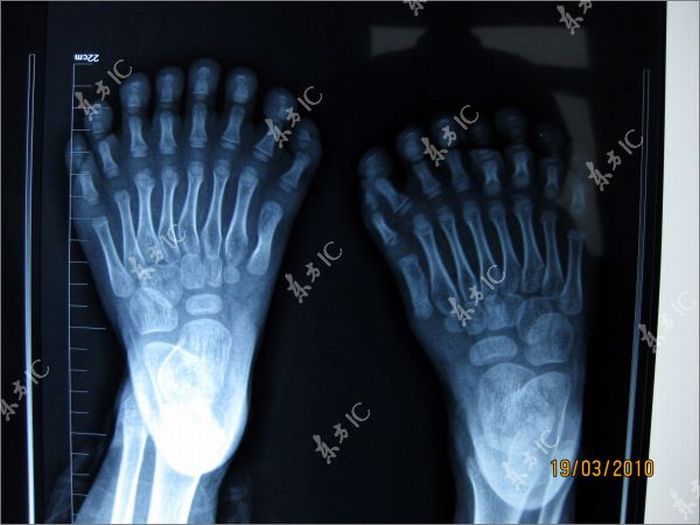

With a total of 31 fingers and toes, the boy, who’s identity hasn’t been revealed, has beaten the previous record of 25. According to scientists, the excess of fingers and toes is a result of gene mutation.